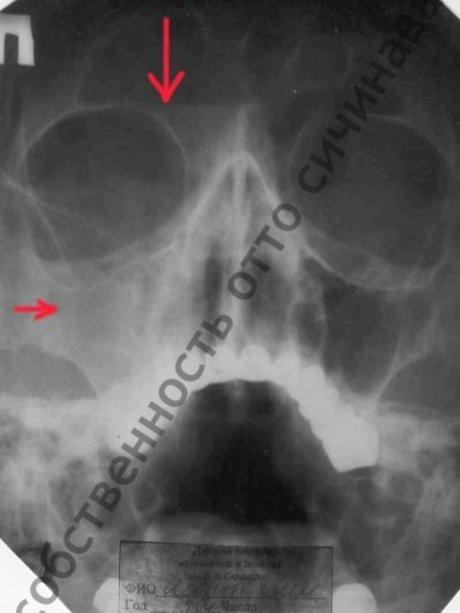

До лечения (виден уровень гноя)

Выше приведены рентгенограммы пациентки Л., проходившей лечение в одной из ЛОР-клиник медицинского института г. Москва. Правая гайморова пазуха полностью заполнена гнойным содержимым, а также есть гной в правой лобной пазухе. Проведенные 8 пункций не дали результата, пациентке было предложено оперативное вмешательство.